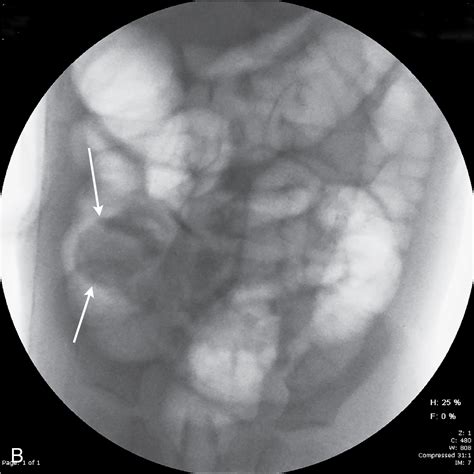

Ultrasound is a valuable tool for diagnosing intussusception, especially in pediatric patients. It provides real-time imaging and can detect the characteristic “target” or “doughnut” sign, which indicates the presence of intussusception. The ultrasound probe is placed on the abdomen, and the radiologist looks for the following signs:

• Target Sign: A hypoechoic outer ring surrounding a hyperechoic inner ring, resembling a target.

• Doughnut Sign: A similar appearance to the target sign but viewed in a transverse section.

• Pseudo-Kidney Sign: An elongated, oval structure resembling a kidney, seen in longitudinal sections.